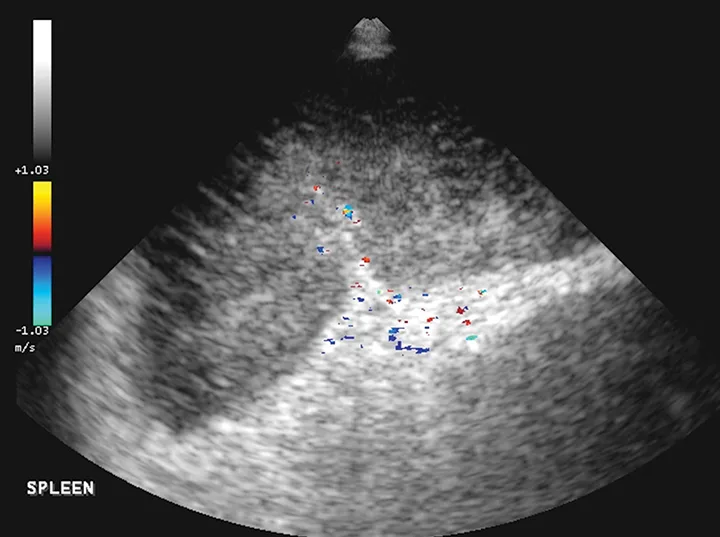

FIGURE 6

The spleen is markedly enlarged, hypoechoic, and lacy, with hyperechoic patches surrounding the hilus. A perivenous hyperechoic triangle at the splenic hilus is continuous with the mesentery, and no flow is present on Doppler. These findings are often associated with splenic torsion.20